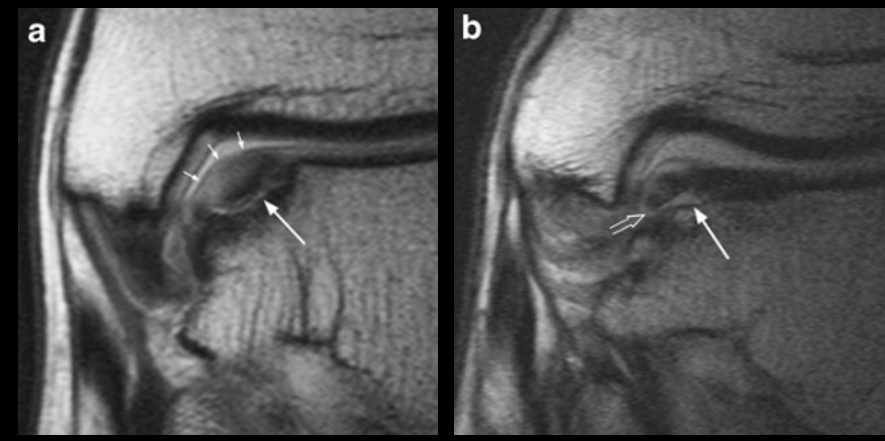

Рис. 4. МРТ: стадии 1а и 1б — повреждение хряща без (1а) и с (1б) вовлечением субхондральной кости

Рис. 5. МРТ: стадии 2а и 2б — субхондральный перелом с отёком костного мозга (2а) и без отёка (2б, хроническое повреждение)

Рис. 6. МРТ: стадии 3а и 3б — отделённый, но не смещённый фрагмент

Рис. 7. МРТ: стадии 4а и 4б — смещённый остеохондральный фрагмент

Рис. 8. МРТ: стадии 5а и 5б — субхондральная киста (хроническое повреждение)